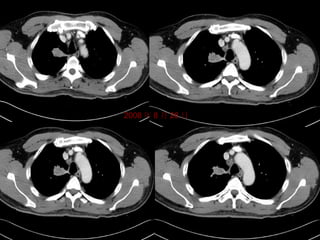

Lung cancer on CT  CT is the most useful in evaluating patients with pulmonary and mediastinal masses. It is also useful for detecting multiple metastases. CT can show a mass to be located in which lobe of lung field and the size of the mass. It also shows the nodule in the mediastinum. Sometimes, when a mass locate behind the heart, chest X-ray can`t detect it .CT can detect some secret sites of lung cancer.

Lung cancer onCT CT is the most useful in evaluating patients with pulmonary and mediastinal masses. It is also useful for detecting multiple metastases. CT can show a mass to be located in which lobe of lung field and the size of the mass. It also shows the nodule in the mediastinum. Sometimes, when a mass locate behind the heart, chest X-ray can`t detect it .CT can detect some secret sites of lung cancer.